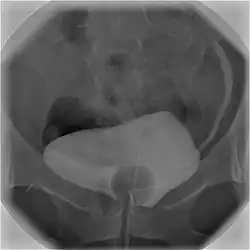

![]() Cystography image showing contrast in the urinary bladder and left ureter (right side of image). | |

Cystourethrography is a radiographic, fluoroscopic medical procedure that is used to visualize and evaluate the bladder and the urethra.[1] Voiding and positive pressure cystourethrograms help to assess lower urinary tract trauma, reflux, suspected fistulas, and to diagnose urinary retention. Magnetic imaging (MRI) has been replacing this diagnostic tool due to its increased sensitivity.[2] This imaging technique is used to diagnose hydronephrosis, voiding anomalies, and urinary tract infections in children. abnormalities.[3]